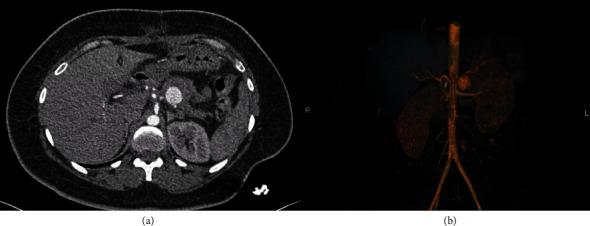

Iatrogenic aneurysms of the splenic artery constitute a rare yet potentially severe complication arising from diverse medical or surgical interventions. The clinical complexity and challenging management strategies associated with these aneurysms pose significant difficulties for clinicians. This circumstance is exemplified in our case report, detailing an iatrogenic aneurysm of the splenic artery that emerged secondary to a pancreatic fistula following a median pancreatectomy performed for a Frantz tumor. The intricate clinical presentation of this case underscores the considerable management challenges posed by such iatrogenic complications.